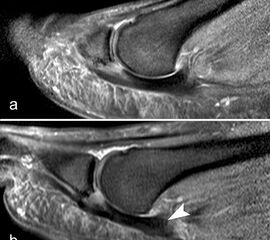

Die sagittalen PD FS Schichten im medialen und lateralen Bereich der plantaren Platte (a, c) zeigen eine völlig unauffällige,  Der kleine Flüssigkeitseinschluss in der Mittellinie der Zehe (b, Pfeil) entspricht einem physiolo

Abbildung 9

Zwischen der plantaren Platte und der Grundphalanx ist in der Mittellinie des Gelenkes ein kleiner Rezessus vorhanden (Abb. 9).

Dieser flüssigkeitsgefüllte Raum darf nicht als Ruptur der plantaren Platte fehlinterpretiert werden 23. Verletzungen der plantaren Platte erfassen immer auch den medialen oder lateralen Zügel.